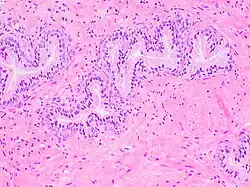

The prostate consists of glandular and connective tissue.[2] Tall column-shaped cells form the lining (the epithelium) of the glands.[2] These form one layer or may be pseudostratified.[4] The epithelium is highly variable and areas of low cuboidal or flat cells can also be present, with transitional epithelium in the outer regions of the longer ducts.[10] Basal cells surround the luminal epithelial cells in benign glands. The glands are formed as many follicles, which drain into canals and subsequently 12–20 main ducts, These in turn drain into the urethra as it passes through the prostate.[4] There are also a small amount of flat cells, which sit next to the basement membranes of glands, and act as stem cells.[2]

The connective tissue of the prostate is made up of fibrous tissue and smooth muscle.[2] The fibrous tissue separates the gland into lobules.[2] It also sits between the glands and is composed of randomly orientated smooth-muscle bundles that are continuous with the bladder.[11]

Histology of normal prostate, H&E stain, with benign features: Glands are rounded to irregularly branching, with an inner layer of epithelial cells surrounded by an outer layer of basal cells. They are surrounded by ample stroma. -

Histology of prostate with gradually increasing simple atrophy from left to right, H&E stain. Crowding and angulation may mimic that of adenocarcinoma, but there is nuclear basophilia rather than atypia, and occasional basal cells can still be seen.